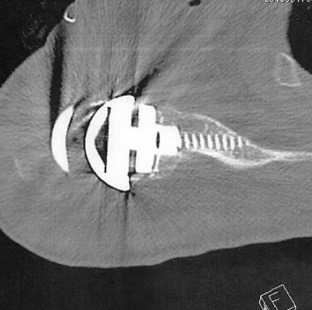

術後CT